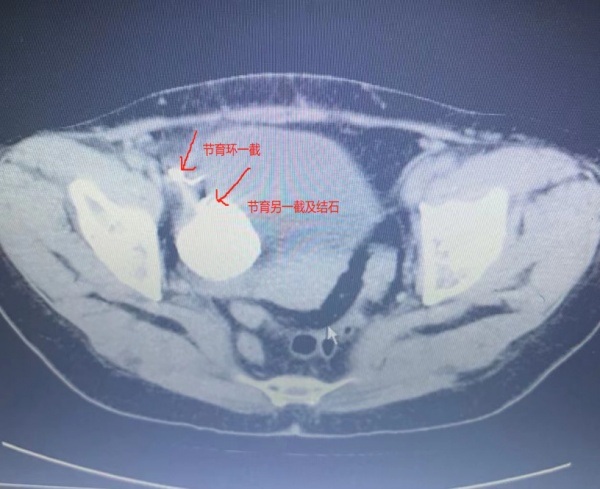

“普通的节育环移位不会伴随尿频尿痛症状多年,陈女士身上可能还存在其他没有发现的问题。”入院后,妇科主任刘海琳及副主任熊志芳第一时间安排陈女士做了腹部盆腔CT检查。检查结果提示:节育环的一端位于膀胱外,另一端位于膀胱内。棘手的是,膀胱内还存在4厘米的大结石与节育环融合。

鉴于陈女士的特殊情况,妇科请来了泌尿外科专家潘炜主任会诊。潘炜结合患者CT片检查结果,与熊志芳及麻醉科甘亚倩副主任协同制定了完备的手术及麻醉方案。